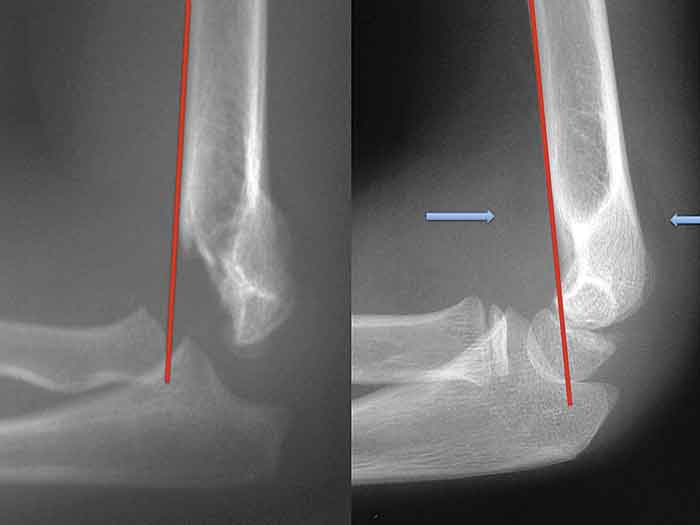

Om man på sidoröntgenbilden lägger en linje utefter humerus längsaxel och någon del av distala humerus ligger framför linjen, är felställningen <20 grader. Är dessutom varus-/valgusfelställningen <10 grader och frakturen minimalt rotationsfelställd behöver den inte reponeras utan kan behandlas konservativt med gips. Frakturläget kontrolleras med röntgen efter 7–9 dagar. Är felställningen större än vad som beskrivits ovan krävs operation [3-6].

Röntgen av armbåge med caput framför respektive bakom linje på framsidan av humerus (till vänster). Flaggande fettkuddar är tecken på hemartros (blå pilar) (till höger).